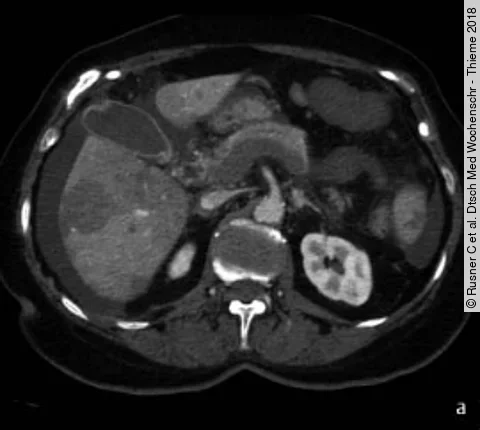

Cetuximab bei fortgeschrittenem Darmkrebs

Eine Interimsanalyse der Phase-3-Studie New EPOC hatte bereits ergeben, dass Patienten mit resektablen Darmkrebsmetastasen in der Leber hinsichtlich des progressionsfreien Überlebens nicht von einer perioperativen Chemotherapie plus Cetuximab im Vergleich zur alleinigen Chemotherapie profitieren. Jetzt liegen die Langzeitergebnisse vor. Sehen Sie…